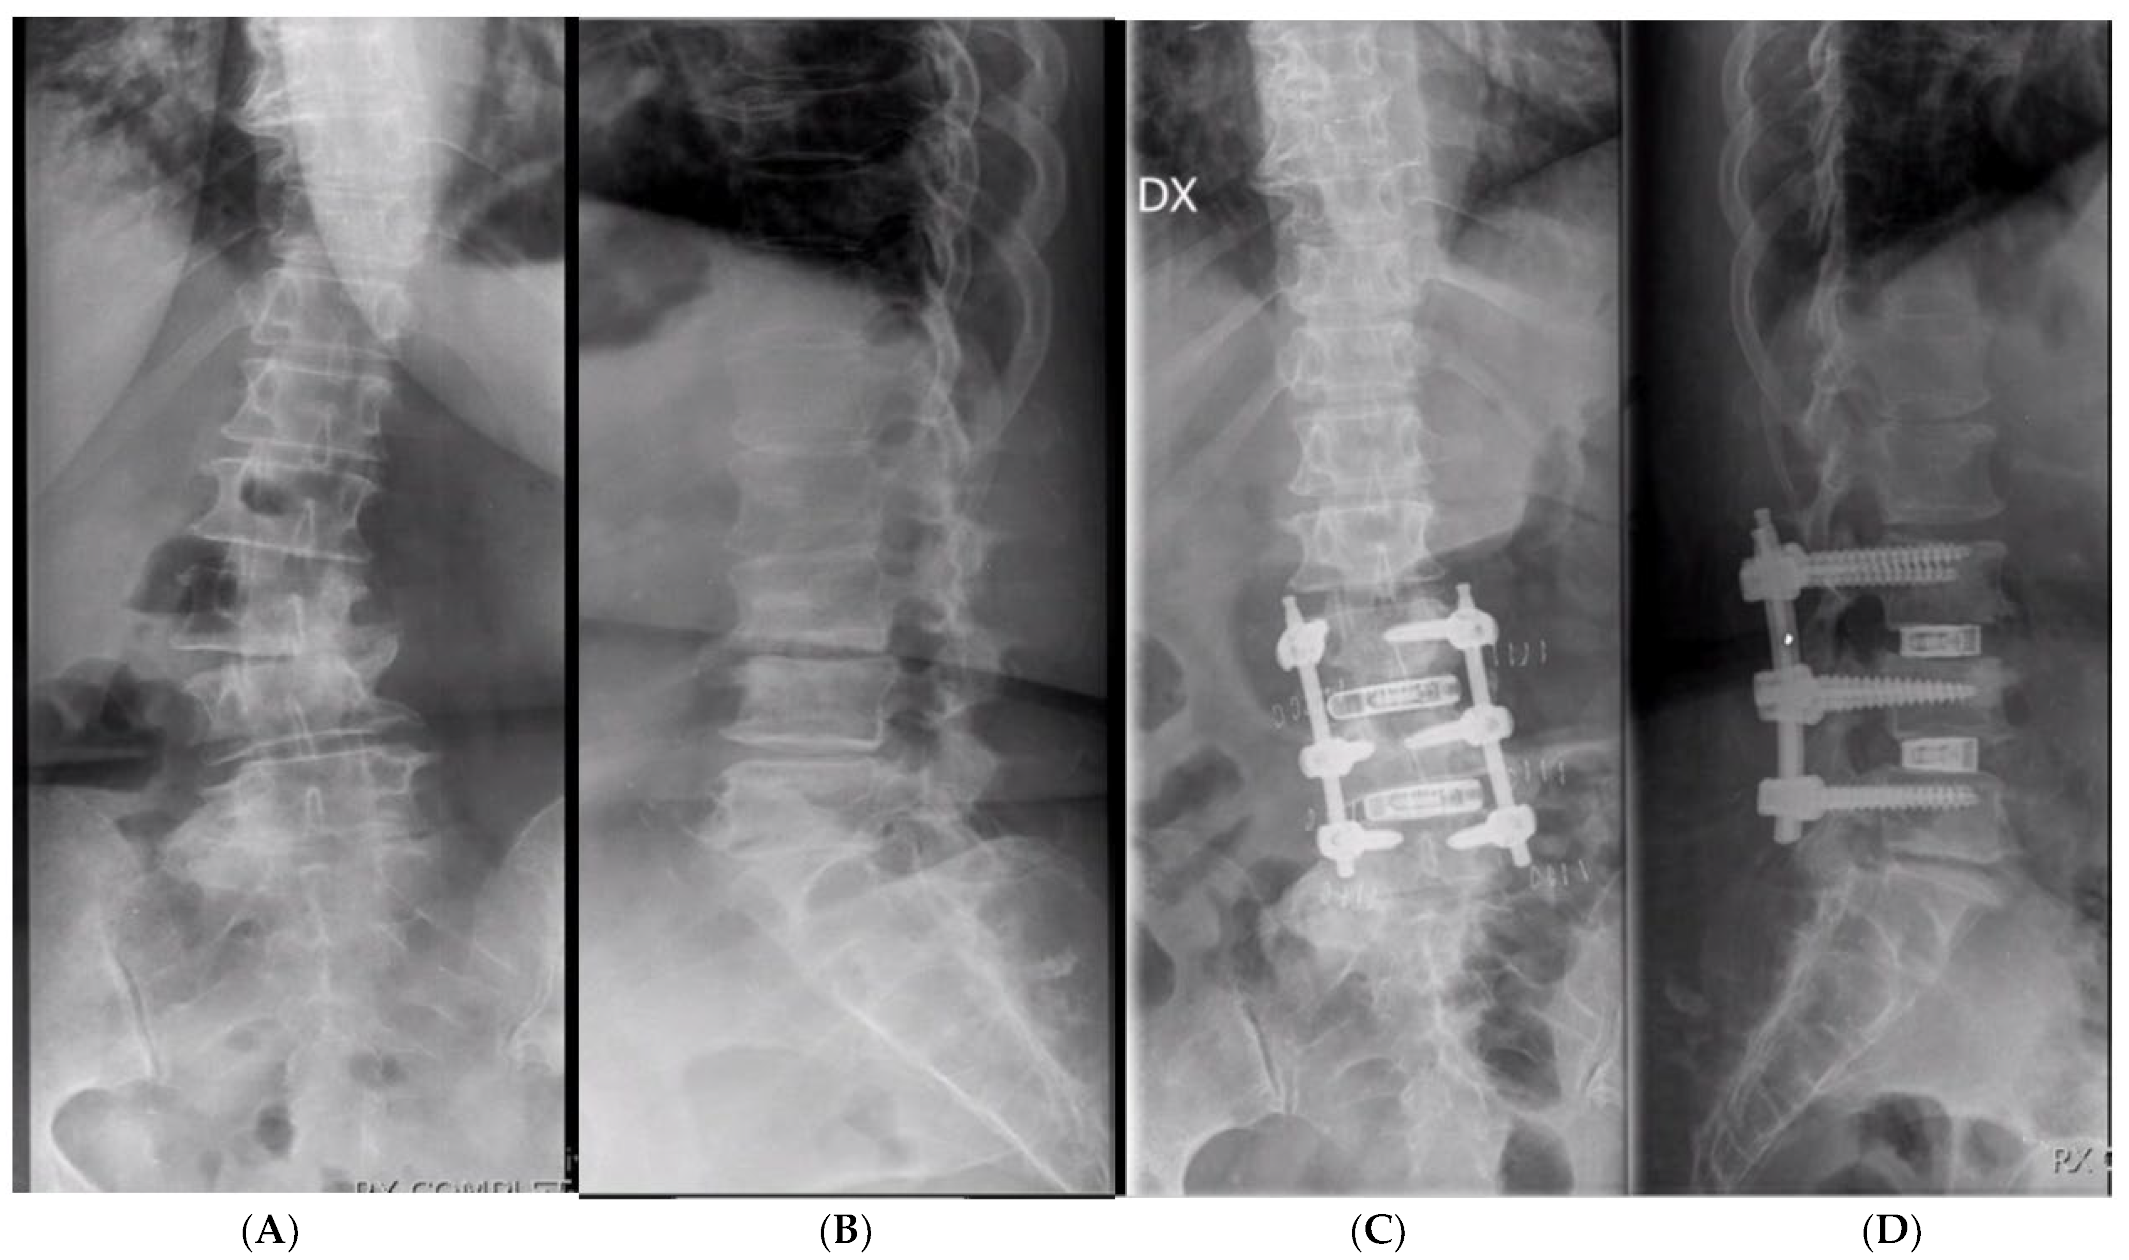

3.2. Clinical and Radiological Outcomes